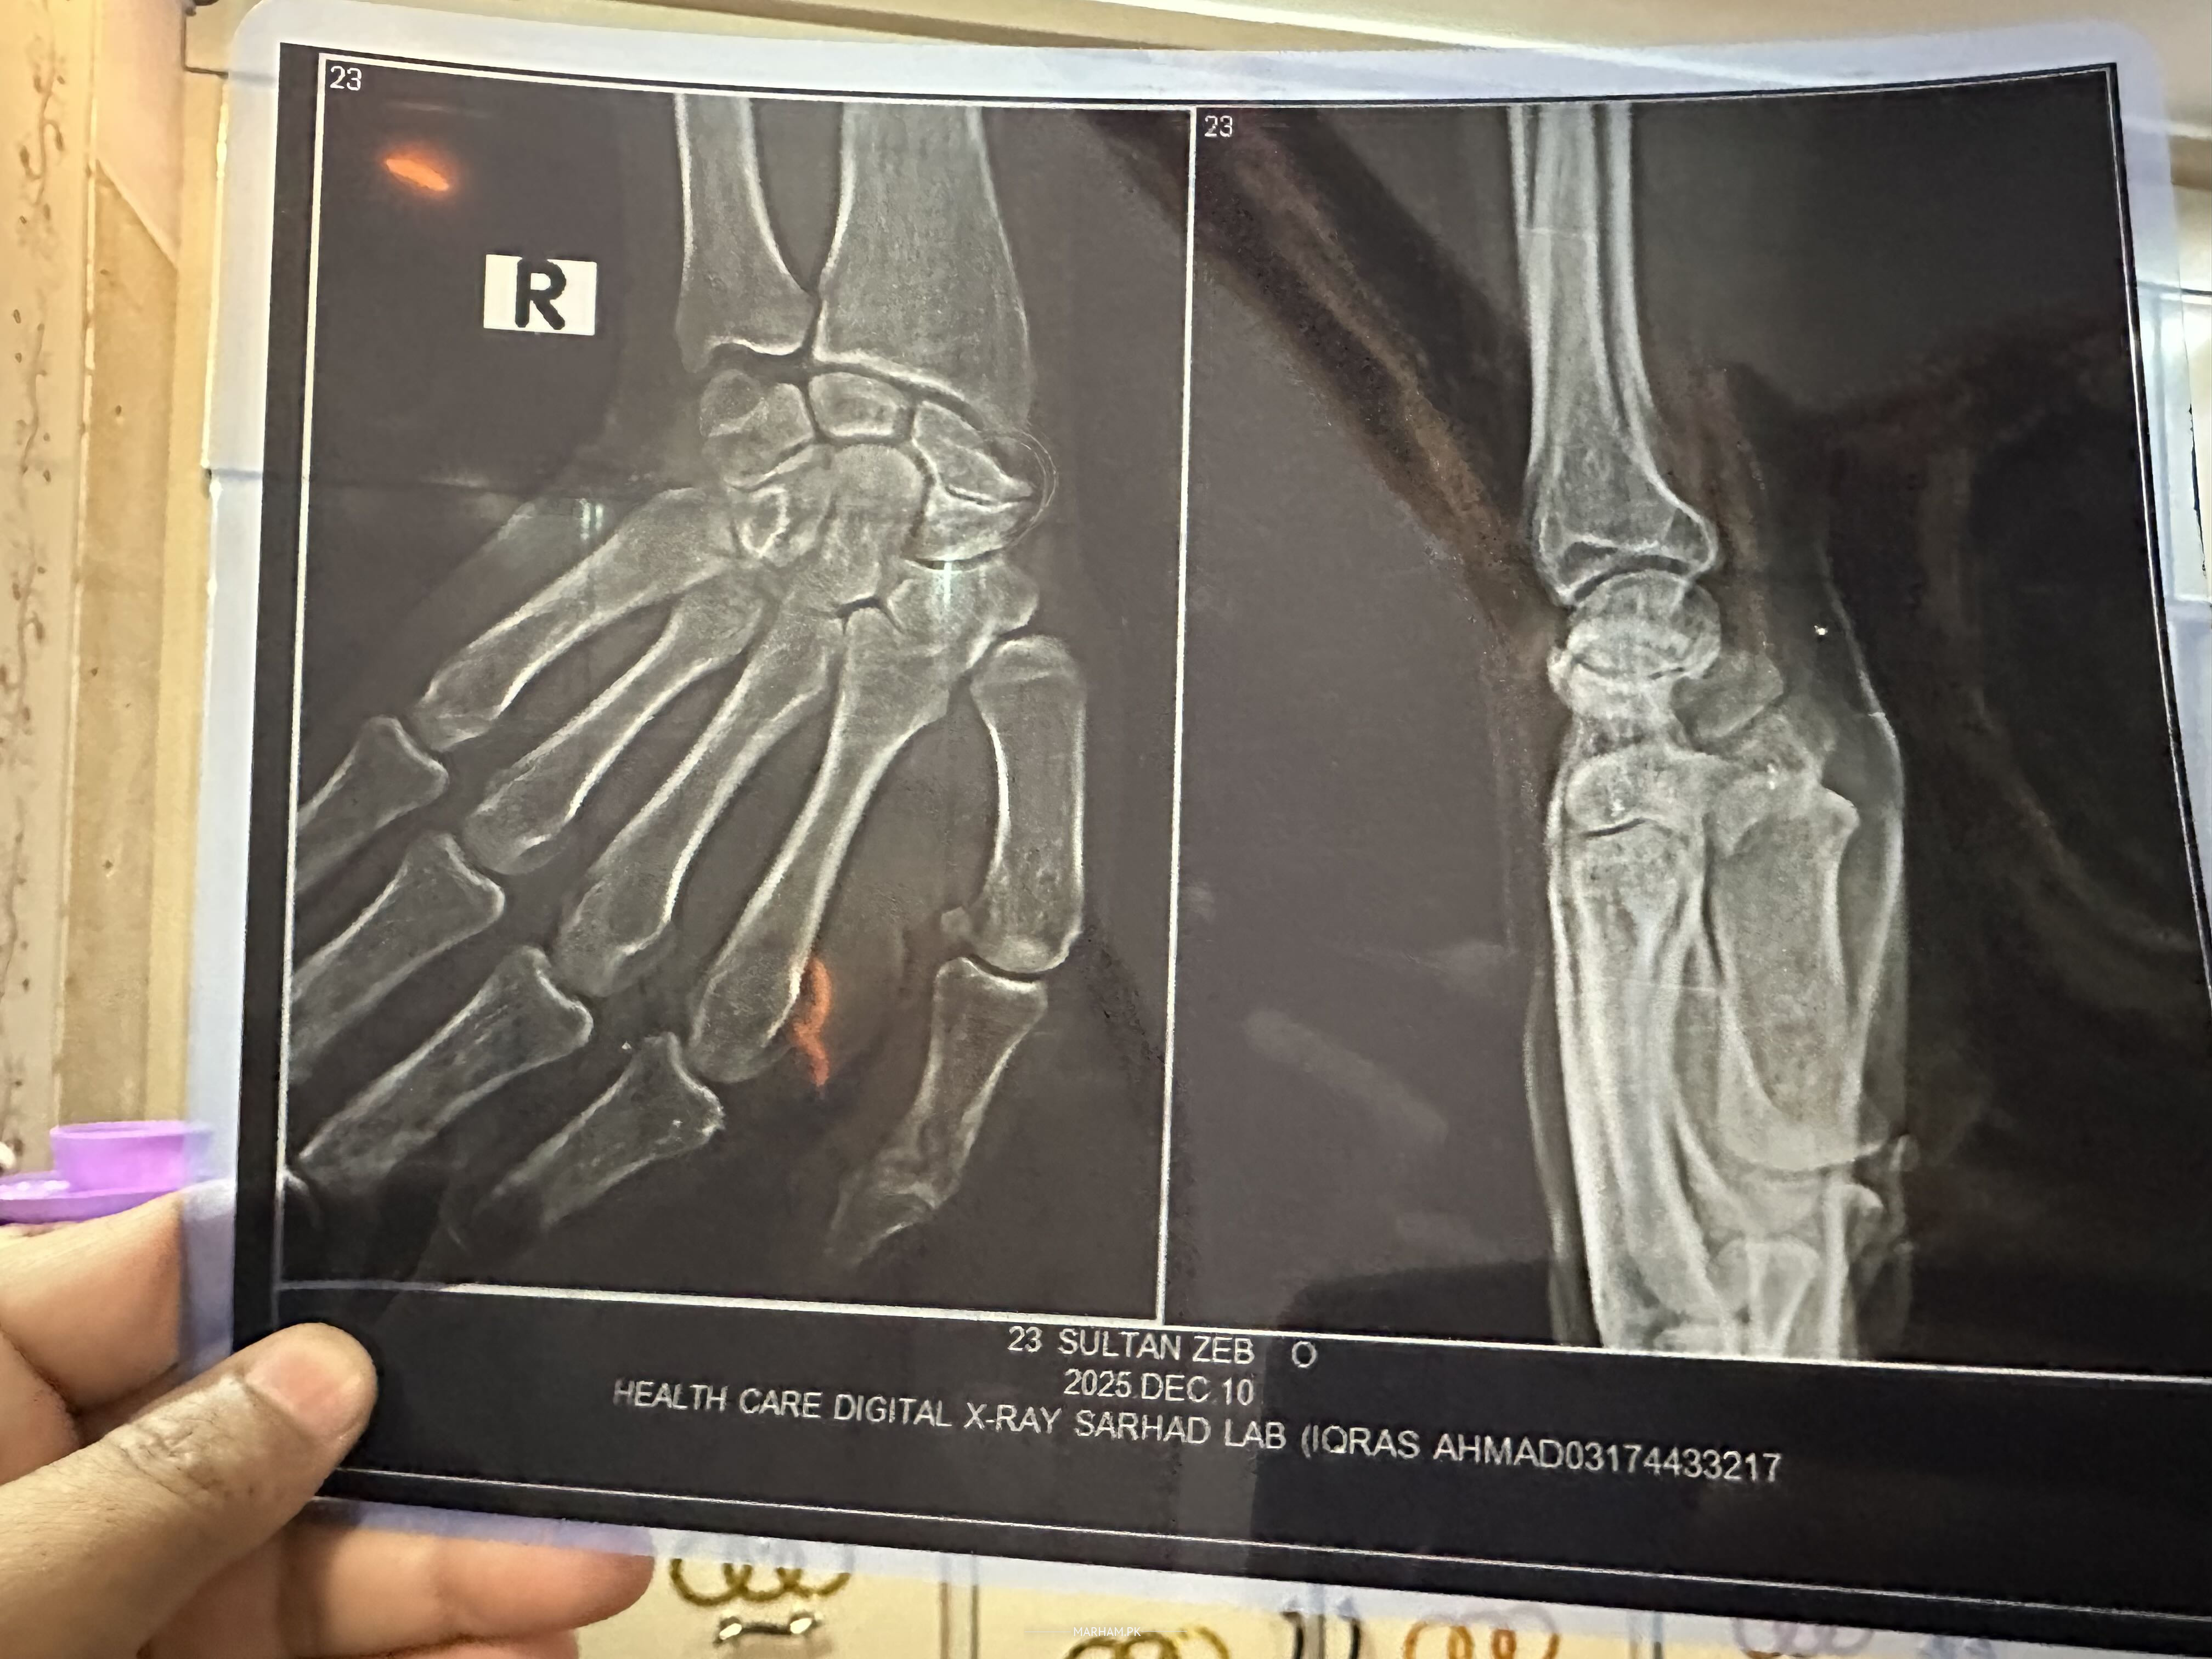

Sir i have a fracture in my right hand dr have suggested surgery please tell me about the cost of surgery please a am attaching x-ray

scaphoid fracture non union

Scaphoid fracture diagnosed

It depends on where you have surgery and what is advised. You have arthritis in wrist

Non united fracture Scaphoid bone. On plain XRAY doesn't look avascular necrosis of fracture bone , but taking into consideration of long duration of this fracture, better to do MRI of your hand , it will not only tell us about the blood supply of the fracture bone , but also tell if there is any arthritis around the fracture bone .

it's old fracture of scaphoid.

surgery is mandatory